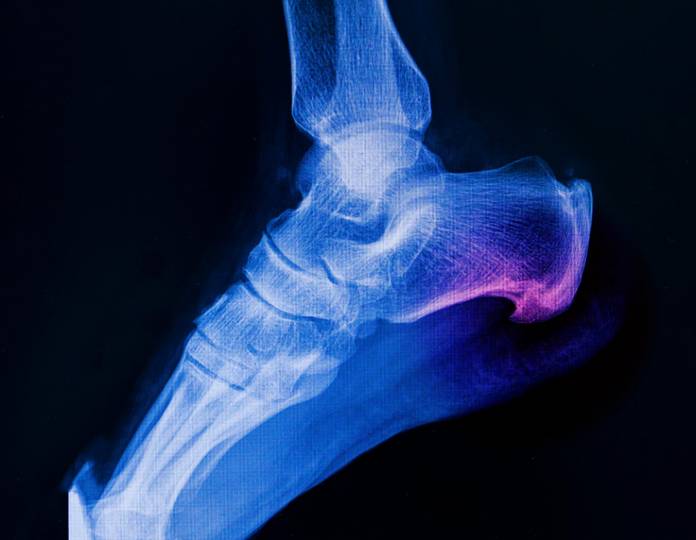

Typische Symptome sind Schwellung Schmerzen und Bewegungseinschränkung im Fuß. Mein Erfahrungsbericht zur Behandlung Operation und Heilungsverlauf nach einem Sprunggelenkbruch.